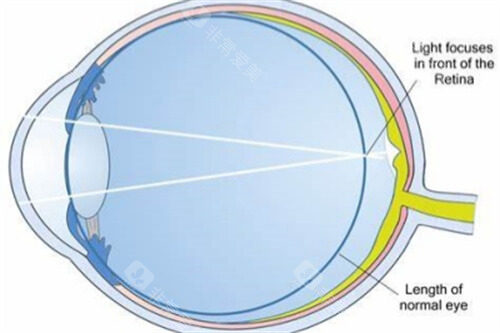

使用特殊的仪器去除角膜上皮,再滴入核黄素眼药水,使角膜充分吸收。

使用紫外线照射角膜,促进角膜胶原纤维交联,增强角膜的强度。

这是因为角膜交联手术后,角膜的形态逐渐稳定,屈光状态也会相应改变。